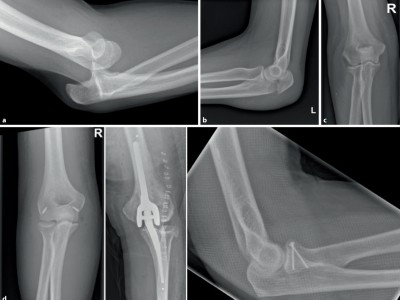

Schulter oder Ellenbogen verletzt: Röntgen oder doch besser gleich eine CT?

Bei Verletzungen am Schulter- oder Ellenbogengelenk liefert die Bildgebung entscheidende Hinweise zur Diagnose – aber nur, wenn Technik und Indikation stimmen. Dieser Beitrag zeigt, welches Verfahren wann sinnvoll ist und warum das konventionelle Röntgen keineswegs verzichtbar ist.

Indikationen zur konventionellen Bildgebung am Ellenbogen/© Rentschler V et al. / all rights reserved Springer Medizin Verlag GmbH, Transrektale MRT/© Springer Medizin, Osteoporotisch bedingte Sinterungsfrakturen der Wirbelsäule/© L. Heuchemer, D. Emmert, T. Bender et al./Springer Medizin Verlag GmbH, Person isst eine Krankenhaus-Mahlzeit/© gballgiggs / Stock.adobe.com (Symbolbild mit Fotomodell), Springer Medizin Podcast - Stürze im Alter/© Gatz M et al / all rights reserved Springer Medizin Verlag, Mann erhält einen CT-Scan /© Mark Kostich / stock.adobe.com (Symbolbild mit Fotomodell), Person hält zwei Tabletten in der Hand/© AsiaVision / Getty Images / iStock (Symbolbild mit Fotomodell), Fallbeispiel Röntgenaufnahme des Thorax in zwei Ebenen/© Reinke L. et al. / all rights reserved Springer Medizin Verlag GmbH, Frau bei Knochenmineraldichte-Messung/© gelmold / stock.adobe.com (Symbolbild mit Fotomodell), Senior im Krankenhausbett mit gebrochenem Fuß/© Mat Hayward / Stock.adobe.com (Symbolbild mit Fotomodell), Abb - Röntgenaufnahme der linken Hüfte anterior-posterior/© K. M. Peters, Ekzem an der Brustwarze/© T. Jansen, Auch der Knochen leidet bei Diabetes - oft schon im mittleren Lebensalter/© Trueffelpix / stock.adobe.com, Ultraschalllängsschnitt der Fossa olecrani/© Springer Medizin Verlag GmbH, Search Icon, Kind streckt sich freudig, Mutter sitzt und lacht/© BioMarin